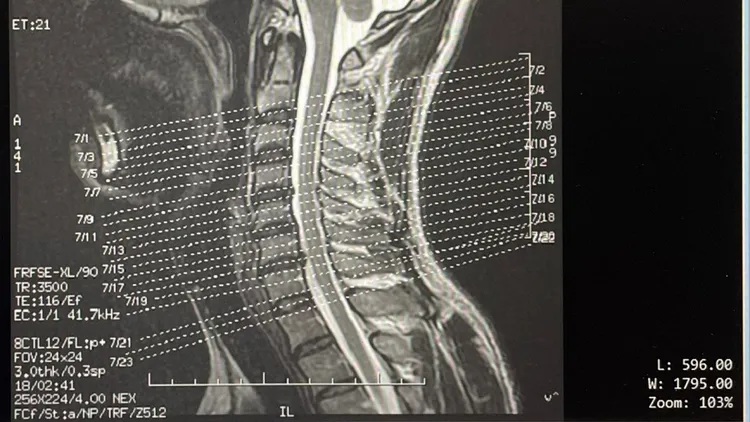

莊智淵還貼出前年所拍攝的核磁共振圖片:1、椎間盤突出跟2015年拍的比較,多了第4~5節間,第5~6節間維持,第6~7節間變嚴重(6~7節之間椎間盤右邊明顯凸(壓)上去)2、第3、4、5節長骨刺,依年紀算退化快。顯然他的宿疾傷害,已瀕臨可承受的臨界點。

他細述,最近做一些動作,像是頭伸直後仰、右手向前平舉,頭轉向同側後更增加反應,初估判斷:間椎盤突出壓迫神經,神經反應在C8-T1最為明顯,神經症狀明顯,於後背脊柱與肩胛骨中、膏肓處、上臂外側、前臂外側及掌外兩根手指皆有劇烈的神經症狀的反應。